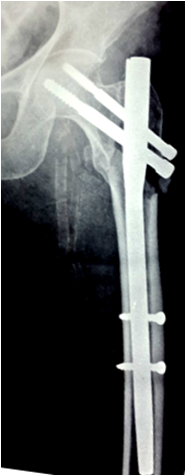

Hip pin and compression screw

Hip pin to be shorter than compression screw. Deep positioning to maintain tip apex distance. Head screws to be tightened alternately for compression. But may sink inside bone (Figure 31,32).

Figure 31 Hip pin to be shorter than compression screw. Deep positioning to maintain tip apex distance.

Figure 32 Head screws to be tightened alternately for compression. But may sink inside bone.